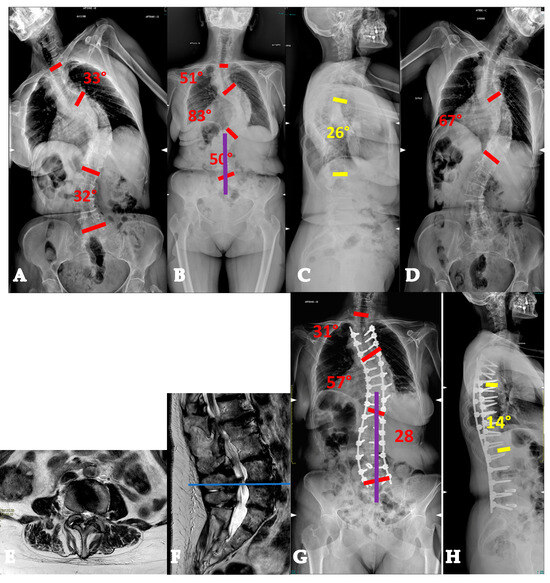

- AdIS 1B: 45–60 years old. These patients usually have a stiffer main curve, with the not infrequent presence of anterior column osteophytes, especially at the concave side. In this setting, combined corrective strategies based on posterior releases (Hi-PoAD [10]) can still achieve an optimal translation, but often, derotation potential is limited, with a possible residual of a partial rib hump (Figure 6).

- AdIS 1C: >60 years old. This is infrequent, since patients in this age group more commonly tend to lie in the AdIS 2 group. This group is burdened by an increased stiffness due to an even more frequent anterior column spontaneous fusion, resulting in a less powerful correction both in terms of translation and derotation, with a consequent smaller correction rate and more prominent residual rib hump. However, it must be considered that these patients more commonly present to surgeons because of pain rather than cosmetic concerns. In this view, pain generators should be carefully identified and adequately treated, performing foraminal and/or central decompressions and discectomies where appropriate (Figure 7).